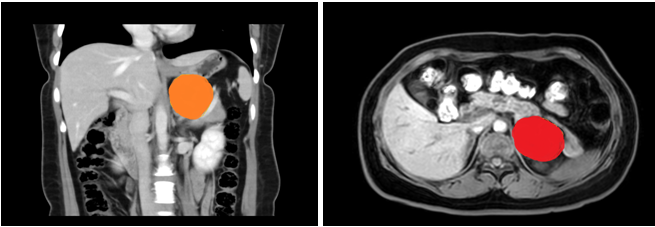

患者,女性,35岁,在黑料网上腹部CT增强示:左侧腹膜后囊性病变,支气管囊肿不除外;入院后上腹部MRI平扫+DWI+增强扫描+MRCP示:左侧肾上腺上方囊性病变,考虑来源腹膜后间隙,1)支气管源性囊肿2)淋巴管囊肿可能,建议复查。

在张煜副主任带领下,经过肝胆外科全科细致讨论,认为占位较大,位置靠后,微创难度大,需完善相关检查,精细术前准备。经过医护一体化管理,打消了患者的术前顾虑,在全麻下行腹腔镜下腹膜后囊性占位手术+广泛腹腔粘连松解术,手术顺利,术后病理结果为良性,患者术后一周内顺利出院。患者表示,术后经过了解,得知此例手术难度较大,目前恢复良好,特意送来锦旗表达感谢。